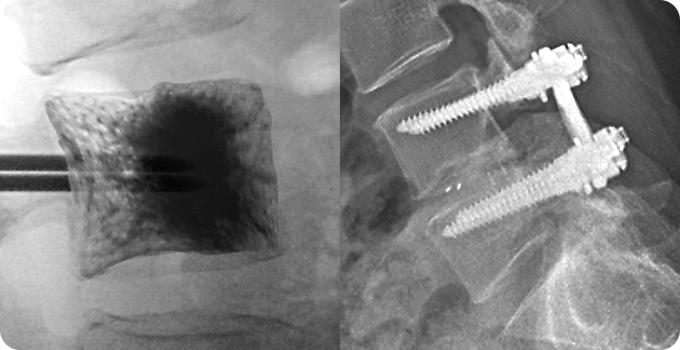

척추 성형술&고정술 사진

3

척추 성형술&고정술

척추 성형술은 의료용 시멘트를 골절 부위에 주입해 통증을 완화하고 척추를 안정화하는 방법입니다. 풍선 척추 성형술은 척추 높이를 복원한 뒤 시멘트를 채워 안정성을 높입니다. 척추 고정술은 금속 기구를 사용해 척추뼈를 고정하며 불안정을 해소합니다. 두 방법 모두 환자의 상태와 골절 정도에 따라 선택됩니다.